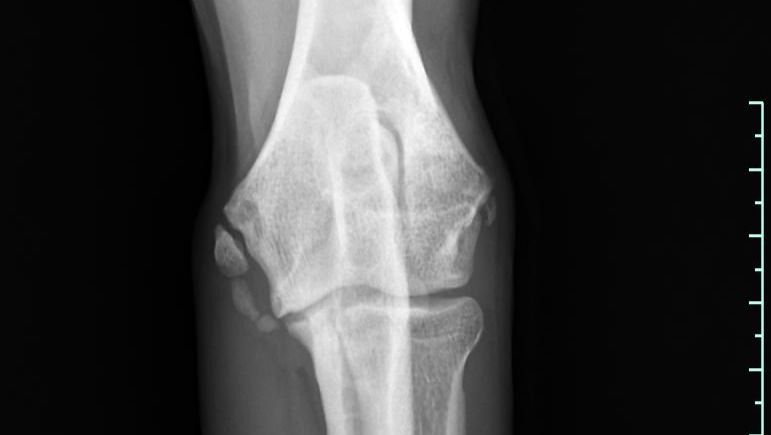

Röntgenaufnahmen und CT-Scans haben zig alte Frakturen und beginnende Arthrosen in seinem jungen Körper aufgedeckt. Ein gerade einmal einjähriger Hund, der bereits mit so vielen physischen Belastungen zu kämpfen hat. Doch die Medizin hat uns nicht im Stich gelassen: Aus seinem Ellbogen wurden Knochenfragmente entfernt, und er bekam ein künstliches Hüftgelenk – ein kleines Wunder der modernen Tiermedizin! Diese Eingriffe bieten ihm die Chance auf ein halbwegs normales Leben.

X-rays and CT scans have revealed countless old fractures and incipient arthrosis in his young body. A dog who is only one year old and already has to deal with so many physical stresses. But medicine has not let us down: bone fragments were removed from his elbow and he received an artificial hip joint - a small miracle of modern veterinary medicine! These operations offer him the chance of a somewhat normal life.